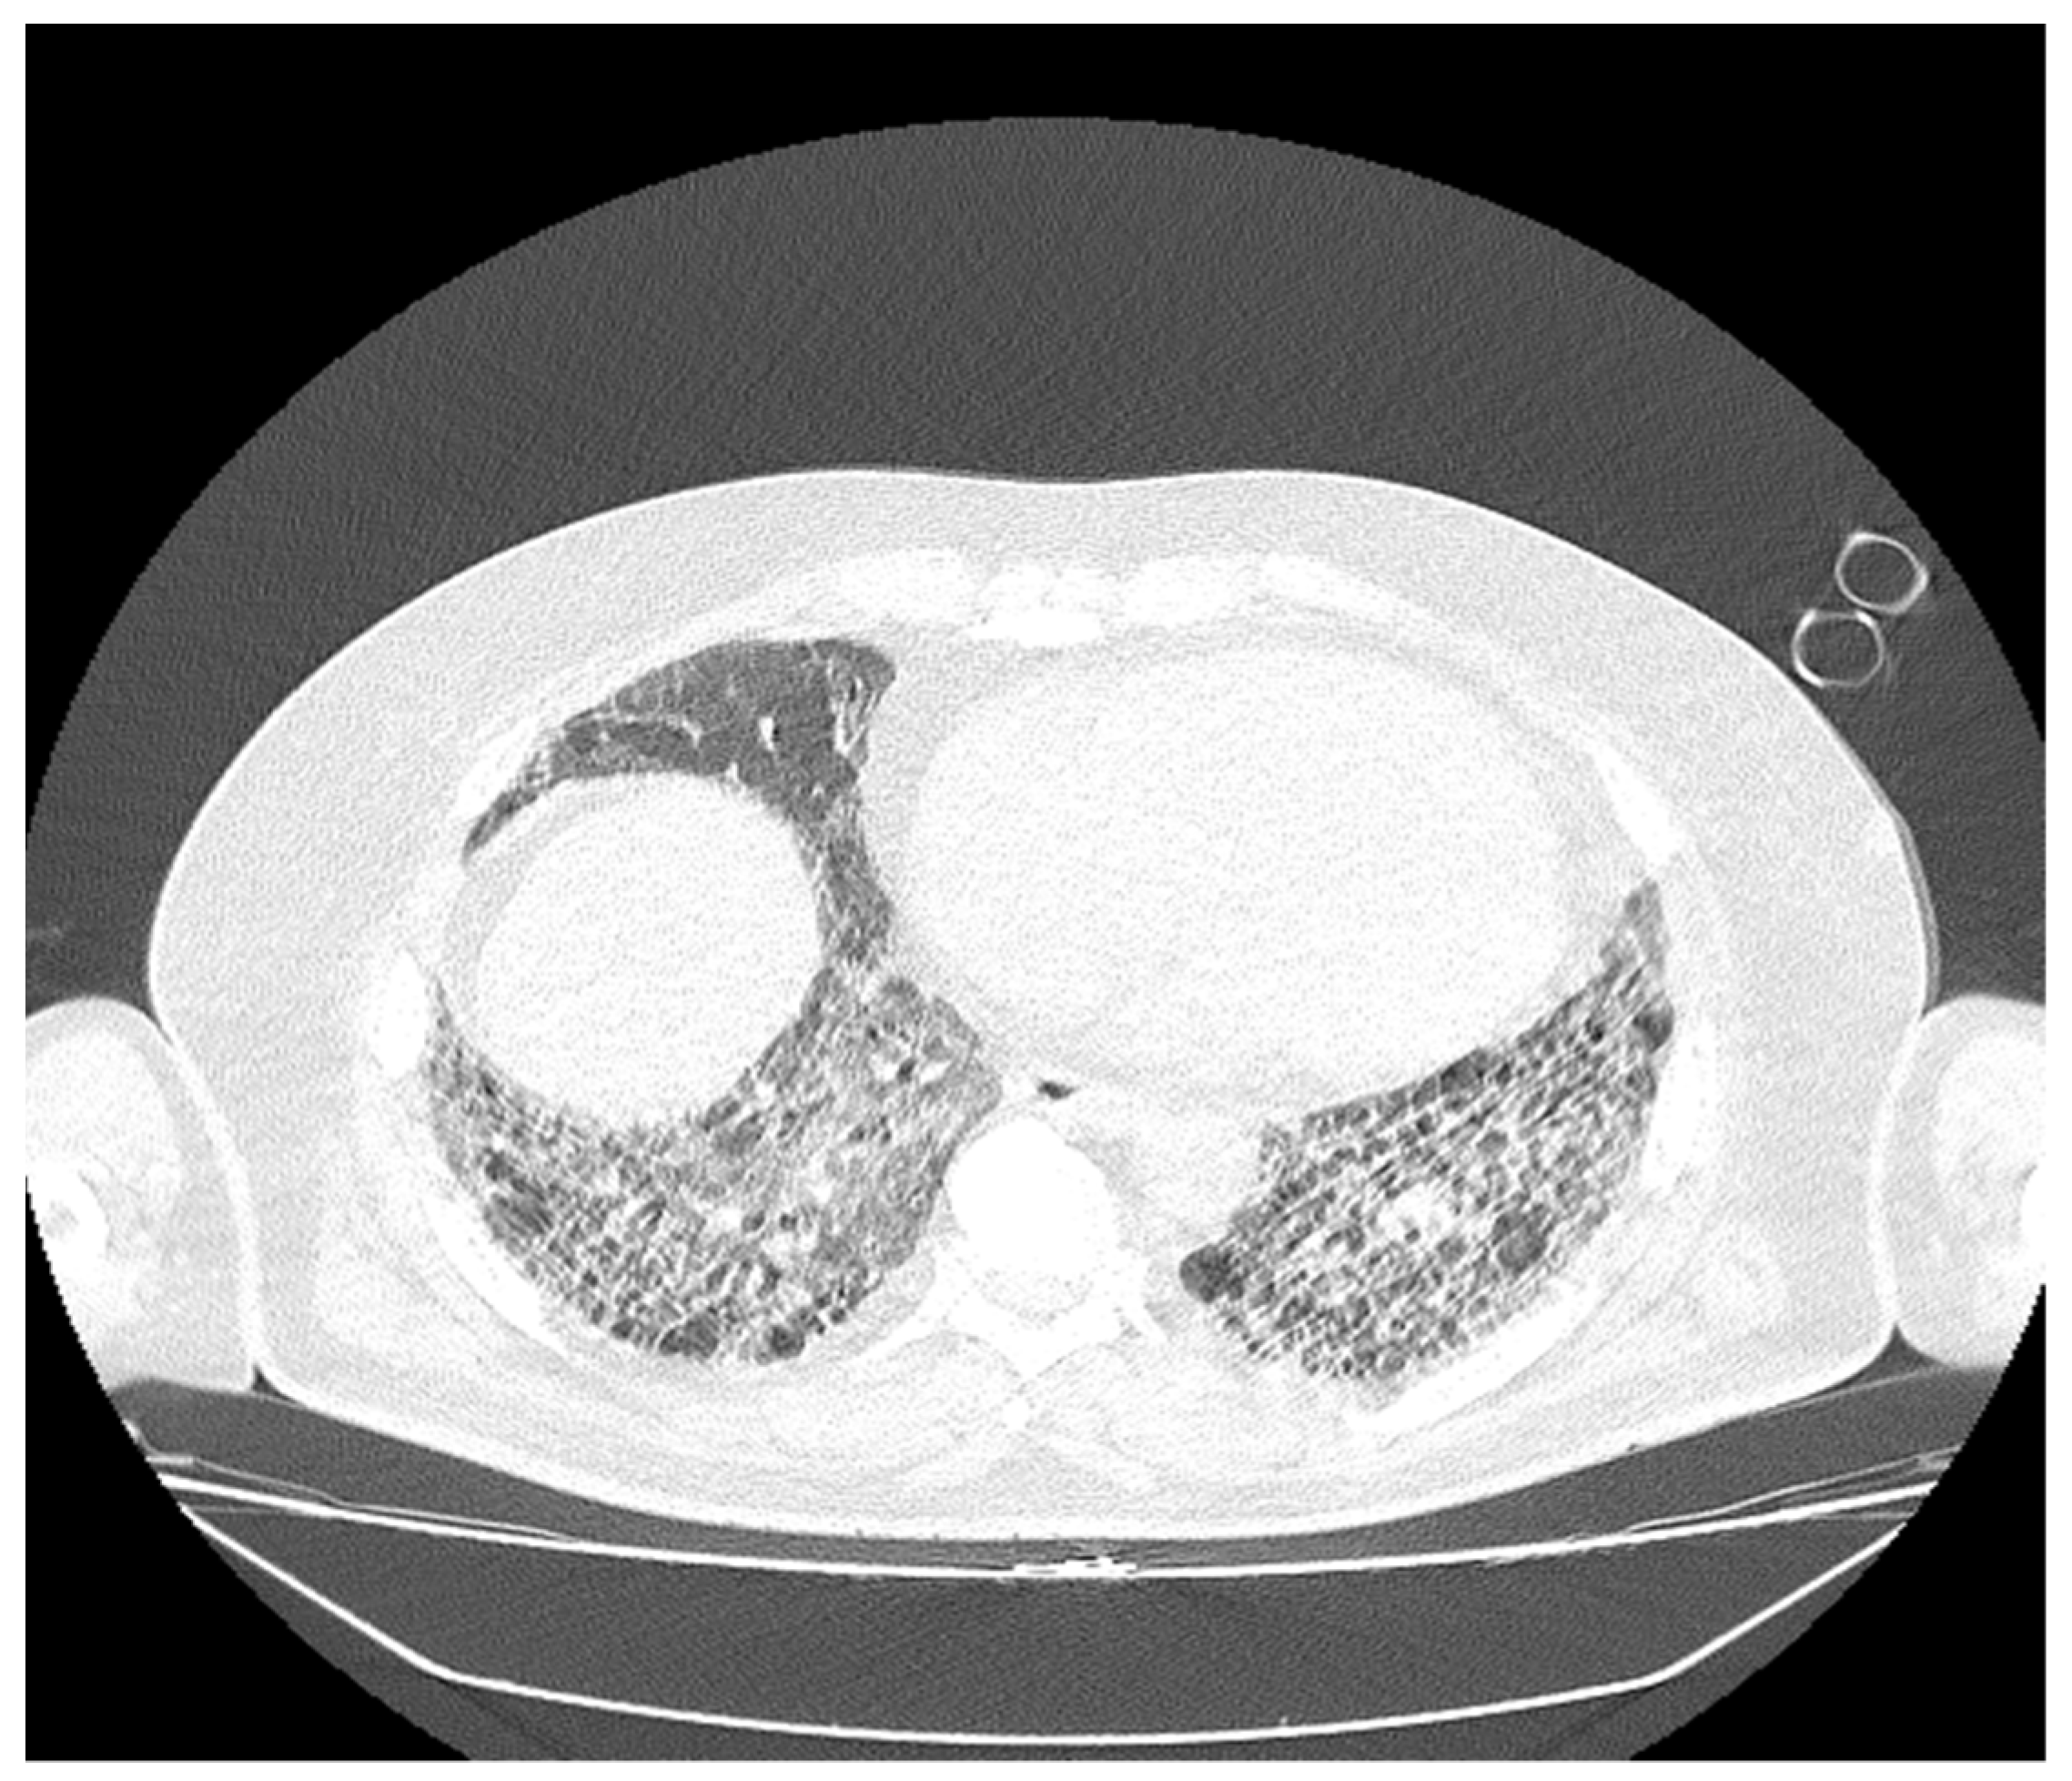

Figure 3. (A,B) Cranio-caudal dispersed reticulonodular opacities, which associate the traction and cylindrical bronchiectasis, on the right lung and cystic on the left basal lung, with an imaging aspect that illustrates end-stage pulmonary fibrosis (UIP pattern). The association of extensive ground-glass opacities is associated with the extensive inflammatory process (NSIP pattern). Global cardiomegaly with a dilated pulmonary trunk shown.

Figure 4. The bilateral pulmonary bases presented dispersed reticulonodular opacities, which associate with traction bronchiectasis: an imaging aspect that illustrates end-stage pulmonary fibrosis (UIP pattern). The association of extensive ground-glass opacities is associated with the extensive inflammatory process (NSIP pattern).